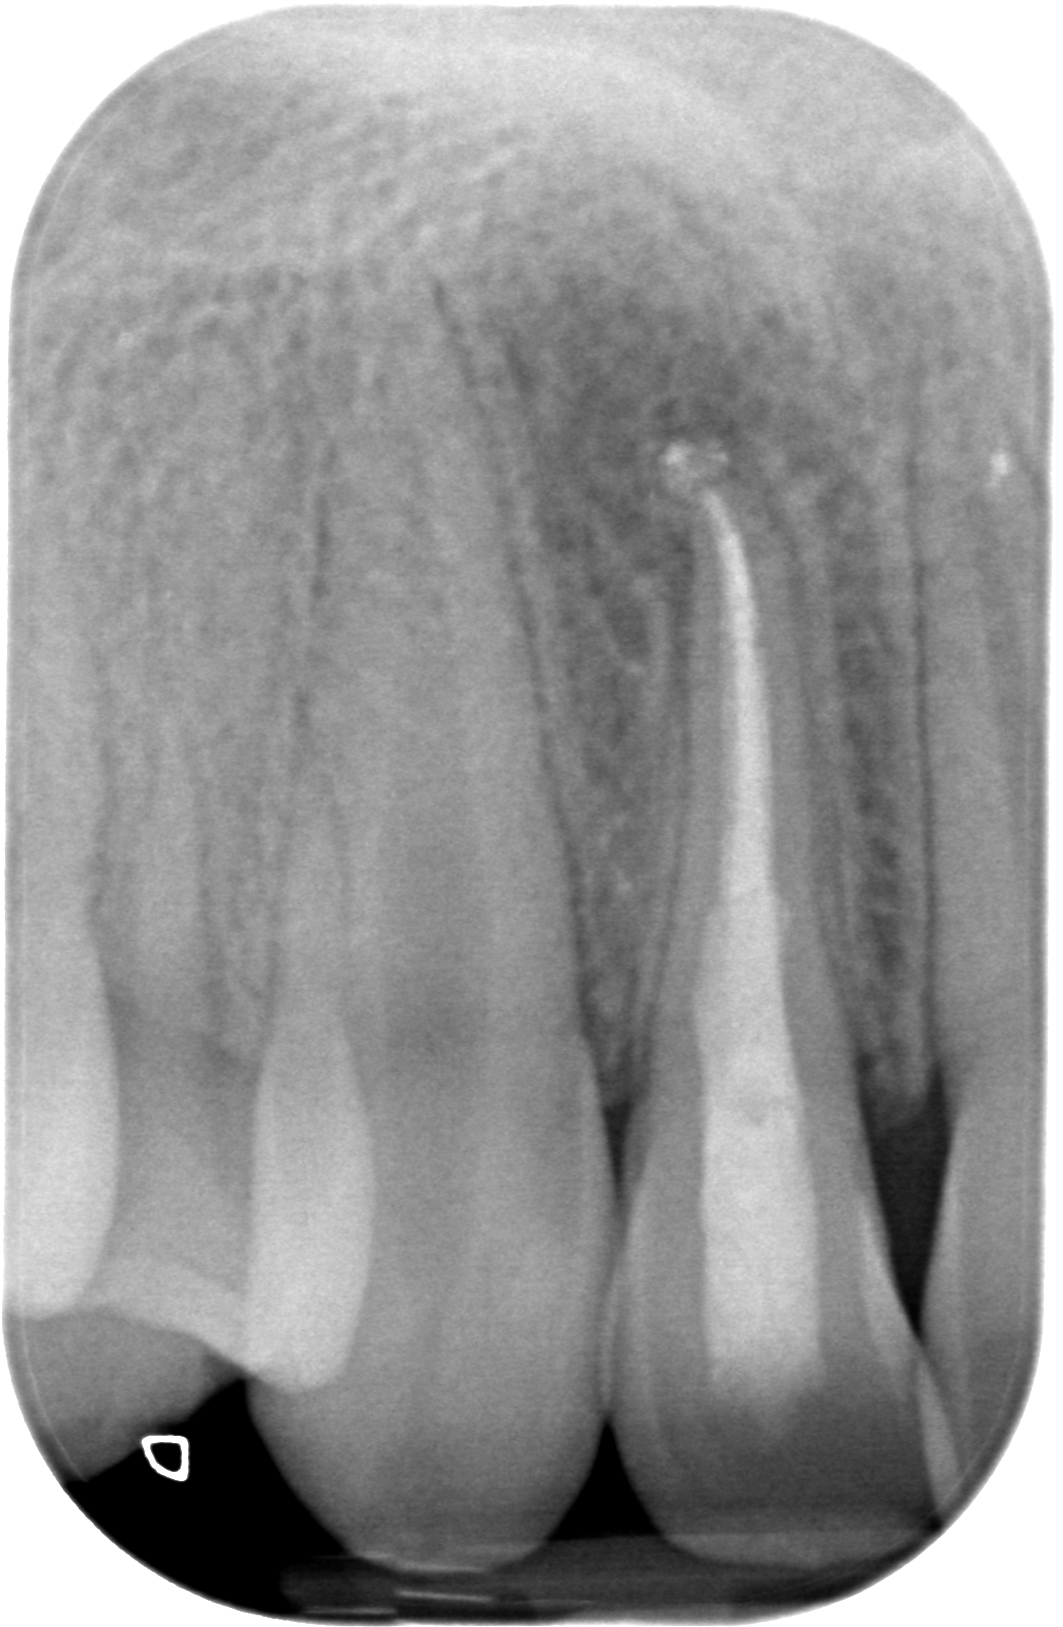

29.04.2019 Patientin LB, geb. am 07.05.2003, Zahn 12, WF-Kontrolle 32 Monate post WF